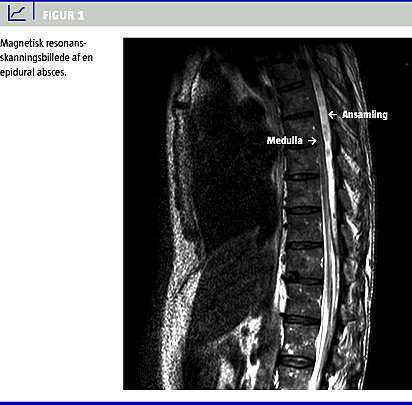

Pga. tiltagende smerter forsøgte man at lægge EPK om til niveau Th 8/Th 9. Proceduren var ukompliceret, men da man kunne aspirere pus fra epiduralrummet, henviste man ham akut til magnetisk resonans (MR)-skanning af medulla spinalis (Figur 1 ) på abscesmistanke. MR-skanningen viste EA, der strakte sig fra Th 3 til Th 12, maks. 8 mm i diameter ud for Th 6 med displacering af medulla.